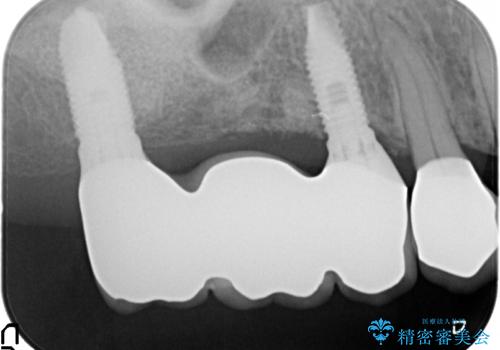

銀歯がセラミッククラウンとなり見た目は美しくなりましたが、審美性だけでなく清掃性も向上し、歯ぐきの状態も良好で、歯周病の再発なく経過しています。

残すことのできる歯できない歯を選別し、欠損部にはインプラントによる咬合機能の回復、保存できる歯には歯周病治療・根管治療を行う治療計画としました。